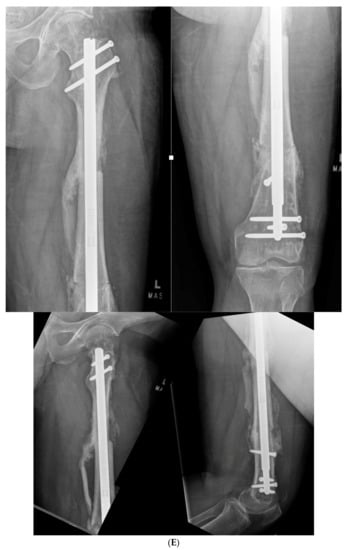

3.2. Case 2-Single-Plane Correction with Plate Fixation: Tibia

A young adult college baseball player presented with symptoms of lateral proximal knee pain and a feeling of knee instability 8 months after sustaining a closed fracture of the tibia, initially treated closed with casting (Figure 7A). The patient underwent a workup including full-length films, knee MRI, and local anesthetic test injection of the proximal tibiofibular joint (relieving knee pain). The CORA analysis revealed a recurvatum deformity of 10 degrees and varus deformity of 3 degrees, with translation in the coronal plane. Full-length alignment film of the pelvis and lower extremity confirmed coronal translation with mild varus angulation (Figure 7B). The true plane of deformity was calculated approximately 75 degrees from the coronal plane (15 degrees off-sagittal) with a magnitude of between 10 and 11 degrees.

(A) A young adult college baseball player sustained a closed tibia fracture with intact fibula, treated closed. The patient developed a recurvatum deformity with pain at the proximal and distal tibiofibular joints. (B) The patient demonstrated mechanical axis lateralization due to coronal plane translation with slight varus. The plane of deformity was calculated as 73 degrees off of the coronal plane. (C) The patient underwent focal dome osteotomy at the CORA (yellow circle) in the plane of maximum deformity. (D) Dual plate compression was used. Angulation and translation were simultaneously corrected. (E) Final follow-up 9 months: anteroposterior, lateral, and oblique films show the osteotomy healed. Tibiofibular joint pain resolved after osteotomy. Patient returned to college-level baseball.

A focal dome was chosen to correct the varus recurvatum and translation. The surgical approach was an anterior approach over the anterior compartment, elevating the tibialis anterior from the lateral tibia to allow safe access to the plane of the deformity. The fibula was osteotomized near the level of the tibia through a separate lateral approach. The plane of maximum deformity was assessed intraoperatively and confirmed the preoperative calculations. The ‘no deformity’ view on fluoroscopy was located, with the maximum plane orthogonal to this. It is in this plane that the drill bit at the CORA is directed, and this is especially important if correcting a translation. The arc of the osteotomy was drawn using a parallel drill guide with one bit centered at the CORA (Figure 7C).

The angulation and translation were simultaneously corrected. Dual medial–lateral plates were used to counteract the lateral gap forming with medial plate compression. Hence, balanced compression from the medial and lateral plates restored the alignment and provided absolute stability (Figure 7D). The patient had immediate relief of knee pain after correction. The soft tissue and osteotomy healed without incident (Figure 7E).